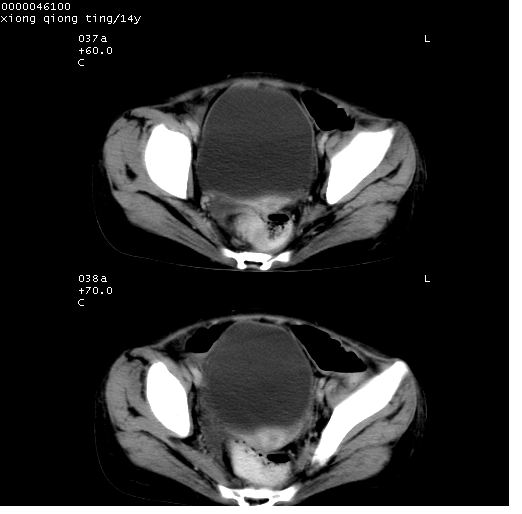

中下腹及盆腔ct轴位平扫+增强扫描(层厚10mm,螺距1.0,重建间隔10mm),图像如下:

(注:患儿检查当日上午9时口服胃肠道对比剂,下午3时许行ct扫描检查,未行对比剂直肠保留灌肠,检查当日患儿腹泻)

中下腹及盆腔ct轴位扫描(ps+ce)提示:腹部肠管明显充气扩张,并见数个不同宽度之气液平面;疑不全性肠梗阻或肠郁张。临床会诊考虑为患儿腹泻,肠郁张所致;后来未经特殊处理,患儿大便恢复正常,亦无腹胀。